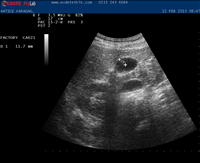

Hizmetimizden görüntüler